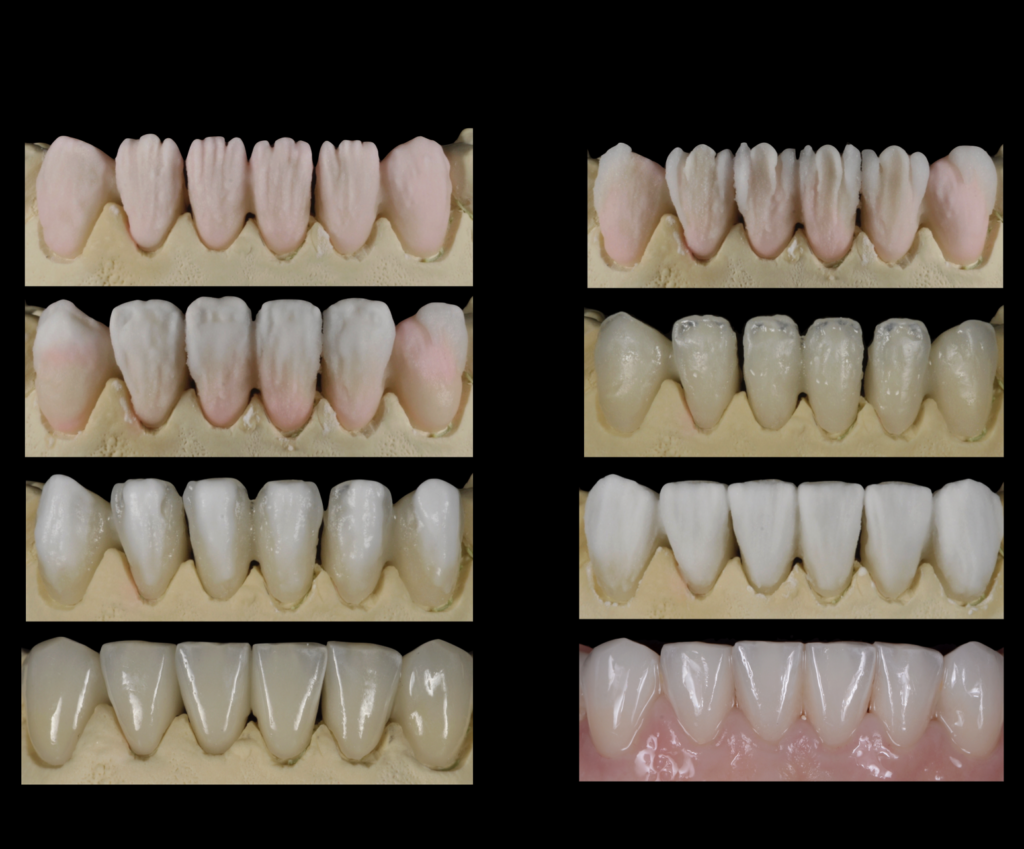

Una vez concluido el estudio de la sonrisa, creamos una simulación real o "mock-up" para que la paciente pudiera visualizar y comprender el resultado final antes de iniciar el tratamiento.

La paciente quedó encantada con el "mock-up", lo que nos permitió comenzar el tratamiento. En este proceso, realizamos un alargamiento coronario para mejorar la sonrisa gingival, ya que exponía demasiada encía. Luego, planificamos y ejecutamos una rehabilitación total cerámica adherida sin metal. Además, reemplazamos las piezas perdidas con implantes dentales, lo que nos permitió restaurar la función y hacer desaparecer los problemas masticatorios y digestivos.